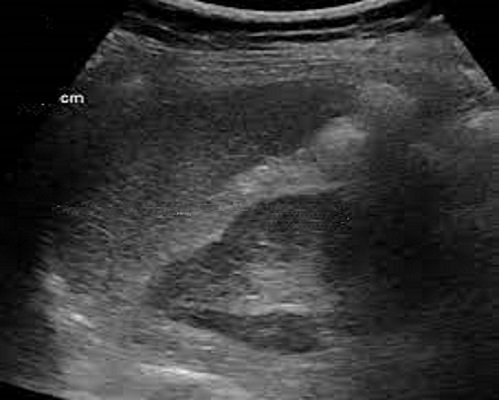

L'Echographie per cutanee et

echographie en Doppler : Echographie

percutane de l'abdomen est la technique de choix de la

premiere dẻ l'intention le plus utilise pour recherche ,

exploree les lesions de la rate , sa indication est

large . Les coupes obliques longitudinale laterale gauche de la ligne axillaire posterieur

a longitudinal et tranversale gauche perpendiculaire de la rate

de 9e,10e et 11e de l'espace intercostale

sont ainsi

utilisés . Aspect echographique est ume organe semi-ovalaire

sur les coupes longitudinale et en forme de croissant

dans les coupes tranversales ; sa diametre longitudinal est de 9,6cm a 12cm , epais de

4,5 cm à moindre < 6cm , sa bord est l;isse bord anterieure

est crenele sa patrenchyme est homogène ,

légèrement hypoéchogène par rapport au foie , hyperéchogene

par rapport au cortex renal . Les veines

splenique sont aechogene.et sa diametre est de moins de 10mm

Coupe echographie

oblique lateral gauche a logitudinal l'axe de la

rate |

Aspect echographique normal de la rate

c'est une organe encasulée en forme de pois ou semi

ovalaire , a bord

lisse , echogenecité homogène à hyperechogène en

rapport avec la cortex du renal et hypoehogène en

rapport avec le foie

|